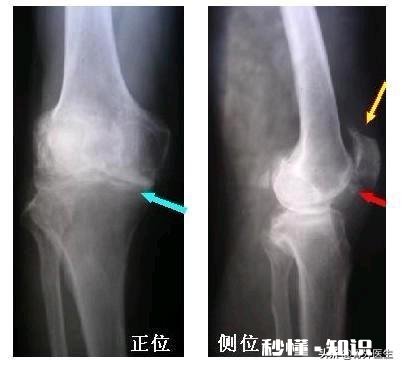

文章插图

半月板分布于膝关节内、外侧,半月板的作用就是可以使膝盖两骨关节面更为适应,以缓冲外力对关节的冲击和震动,还可以改变关节的运动形式,增大关节活动范围 。

解剖显示:关节软骨是位于关节腔内两关节面之间,膝关节软骨呈半月状,故有“半月板”之称 。而半月板的生理特点之一就是不可再生性 。所以机体各部位软骨的保护,永远大于患病后的修复 。

由于软骨本身没有血管和神经,所以初期磨损基本感觉不到什么痛苦,直到磨损到一定程度,软骨下的神经裸露时才有痛感,并且磨损的软骨杂质会堆积于关节周围,刺激周围组织发炎,加重关节疼痛 。